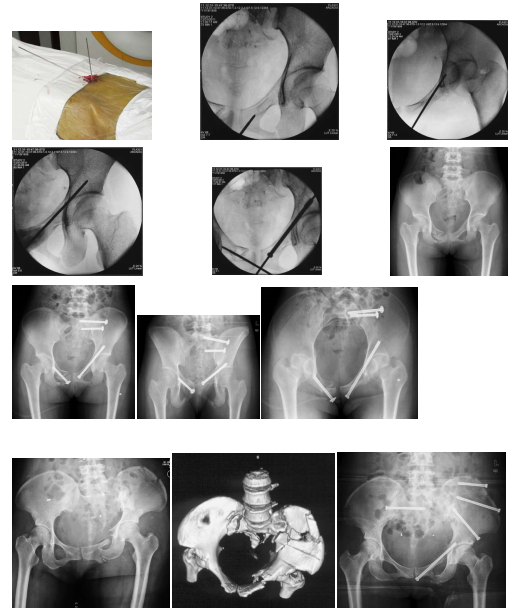

以下图片是我科骨盆骨折的闭合复位经皮通道螺钉微创治疗技术的一例患者资料

图:A、B、C、D术前X光片

图:E、F、G术前CT

图:H术前透视标记

图:I、J、K、L、M、N、O、P、Q、R术中操作透视

图:S手术切口外观

图:T术后X光片

图:U、V、W、X、Y、Z术后CT